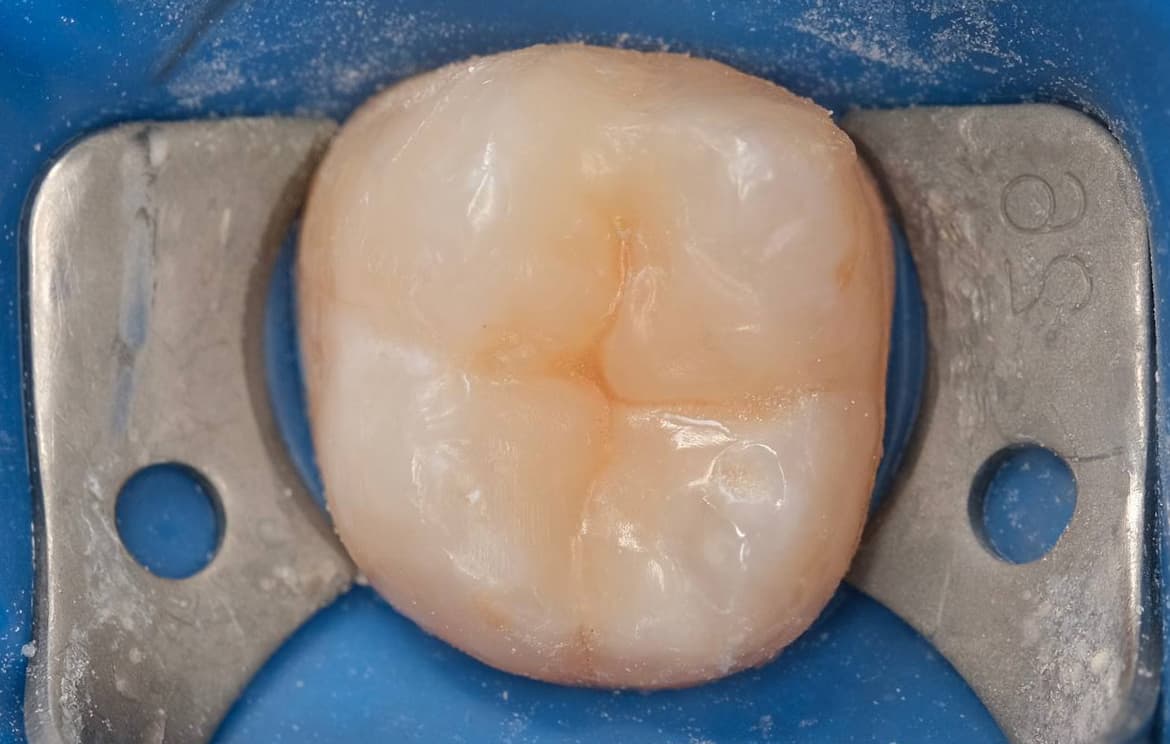

Наши работы